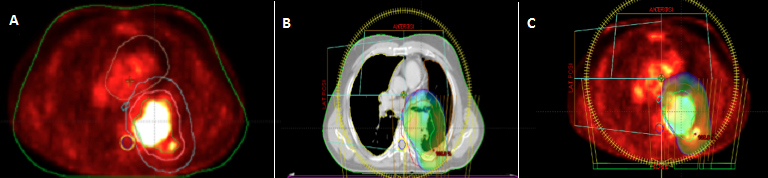

A 56-year-old Arabic man, with a 30 pack-year (1pack/day for 30 years) smoking history, admitted to the department of radiation oncology of military teaching hospital of Rabat for management of locally advanced non small cell cancer of the left lung (Adenocarcinoma). Computerized tomography (CT) of the chest showed a mass involving left upper lobe,measuring 6x7 cm in diameter and infiltrating the vertebral body. Workup including brain MRI and PET-CT, doesn't found lymphadenopathy in the mediastina or distant metastasis, the tumor was hyper metabolic (figure A). The disease was staged T4N0M0. A decision was made to proceed with chemo radiotherapy with curative aim, at the dose of 66 Gy, in 33 fractions of 2Gy, five fractions per week. The proximity of the target volume to the spinal cord,whose dose tolerance should not exceed 45 Gy, makes it impossible to achieve this radiation therapy with conventional technique using simple beams even with 3D conformal method. A treatment by volumetric modulated arc radiation therapy (Rapid arc) was initiated, and the use of two arcs allowed the optimal coverage of the target volume by isodoseline 95% without exceeding the permissible level dose in the spinal cord (figures B, C). Through this case, we aim to encourage acquisition of innovating technologies like Rapidarc by developing countries especially in Africa.